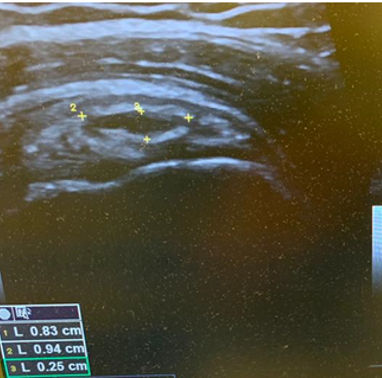

On the dorsum of the foot, ultrasound demonstrated marked cortical irregularity and callus formation around the third metatarsal shaft accounting for the palpable ‘lump’ with surrounding soft tissue swelling (Figure 1). On power Doppler, there was marked peripheral vascularity in the surrounding soft tissues (Figure 2). Incidentally, there was also cortical irregularity and callus formation around the second metatarsal shaft although the patient was not particularly tender here whilst scanning (Figure 3). The cortical irregularity in the second metatarsal shaft was minimal when compared to the third metatarsal and there was no neovascularisation on power Doppler indicating this was an older/mature injury.

Ultrasound appearances in keeping with acute and chronic stress fractures. A radiograph confirmed old and new callus formation (Figure 4). Conservative treatment comprised rest and analgesia. Surgery is generally reserved for stress fractures that do not heal.